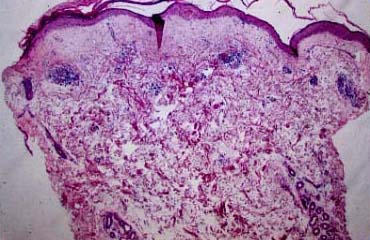

Subacute cutaneous lupus erythematosus = الذئبة الحمامية الجلدية تحت الحادة